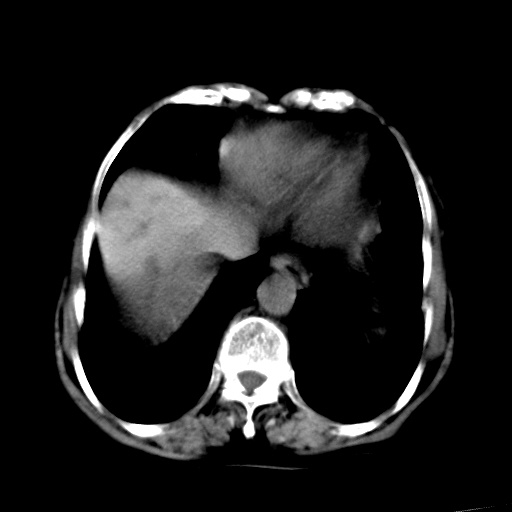

以下是引用杀毒软件在2009-3-4 17:38:00的发言:[br]为何没有喝照影剂呀? 胆总管及肝内胆管扩张,增强吧。[br][br]考虑-----十二指肠占位----建议----十二指肠镜检查[br][br]

以下是引用jiangjing在2009-3-4 17:45:00的发言:[br]低位胆道梗阻。十二指肠降段局部管壁增厚。扫描效果不理想,建议ct增强及ercp。

以下是引用杀毒软件在2009-3-4 17:38:00的发言:[br]为何没有喝照影剂呀? 胆总管及肝内胆管扩张,。增强吧。[br][br]考虑-----十二指肠占位----建议----十二指肠镜检查[br][br][br][br][本贴已被 杀毒软件 于 2009-3-4 17:56:38 修改过]